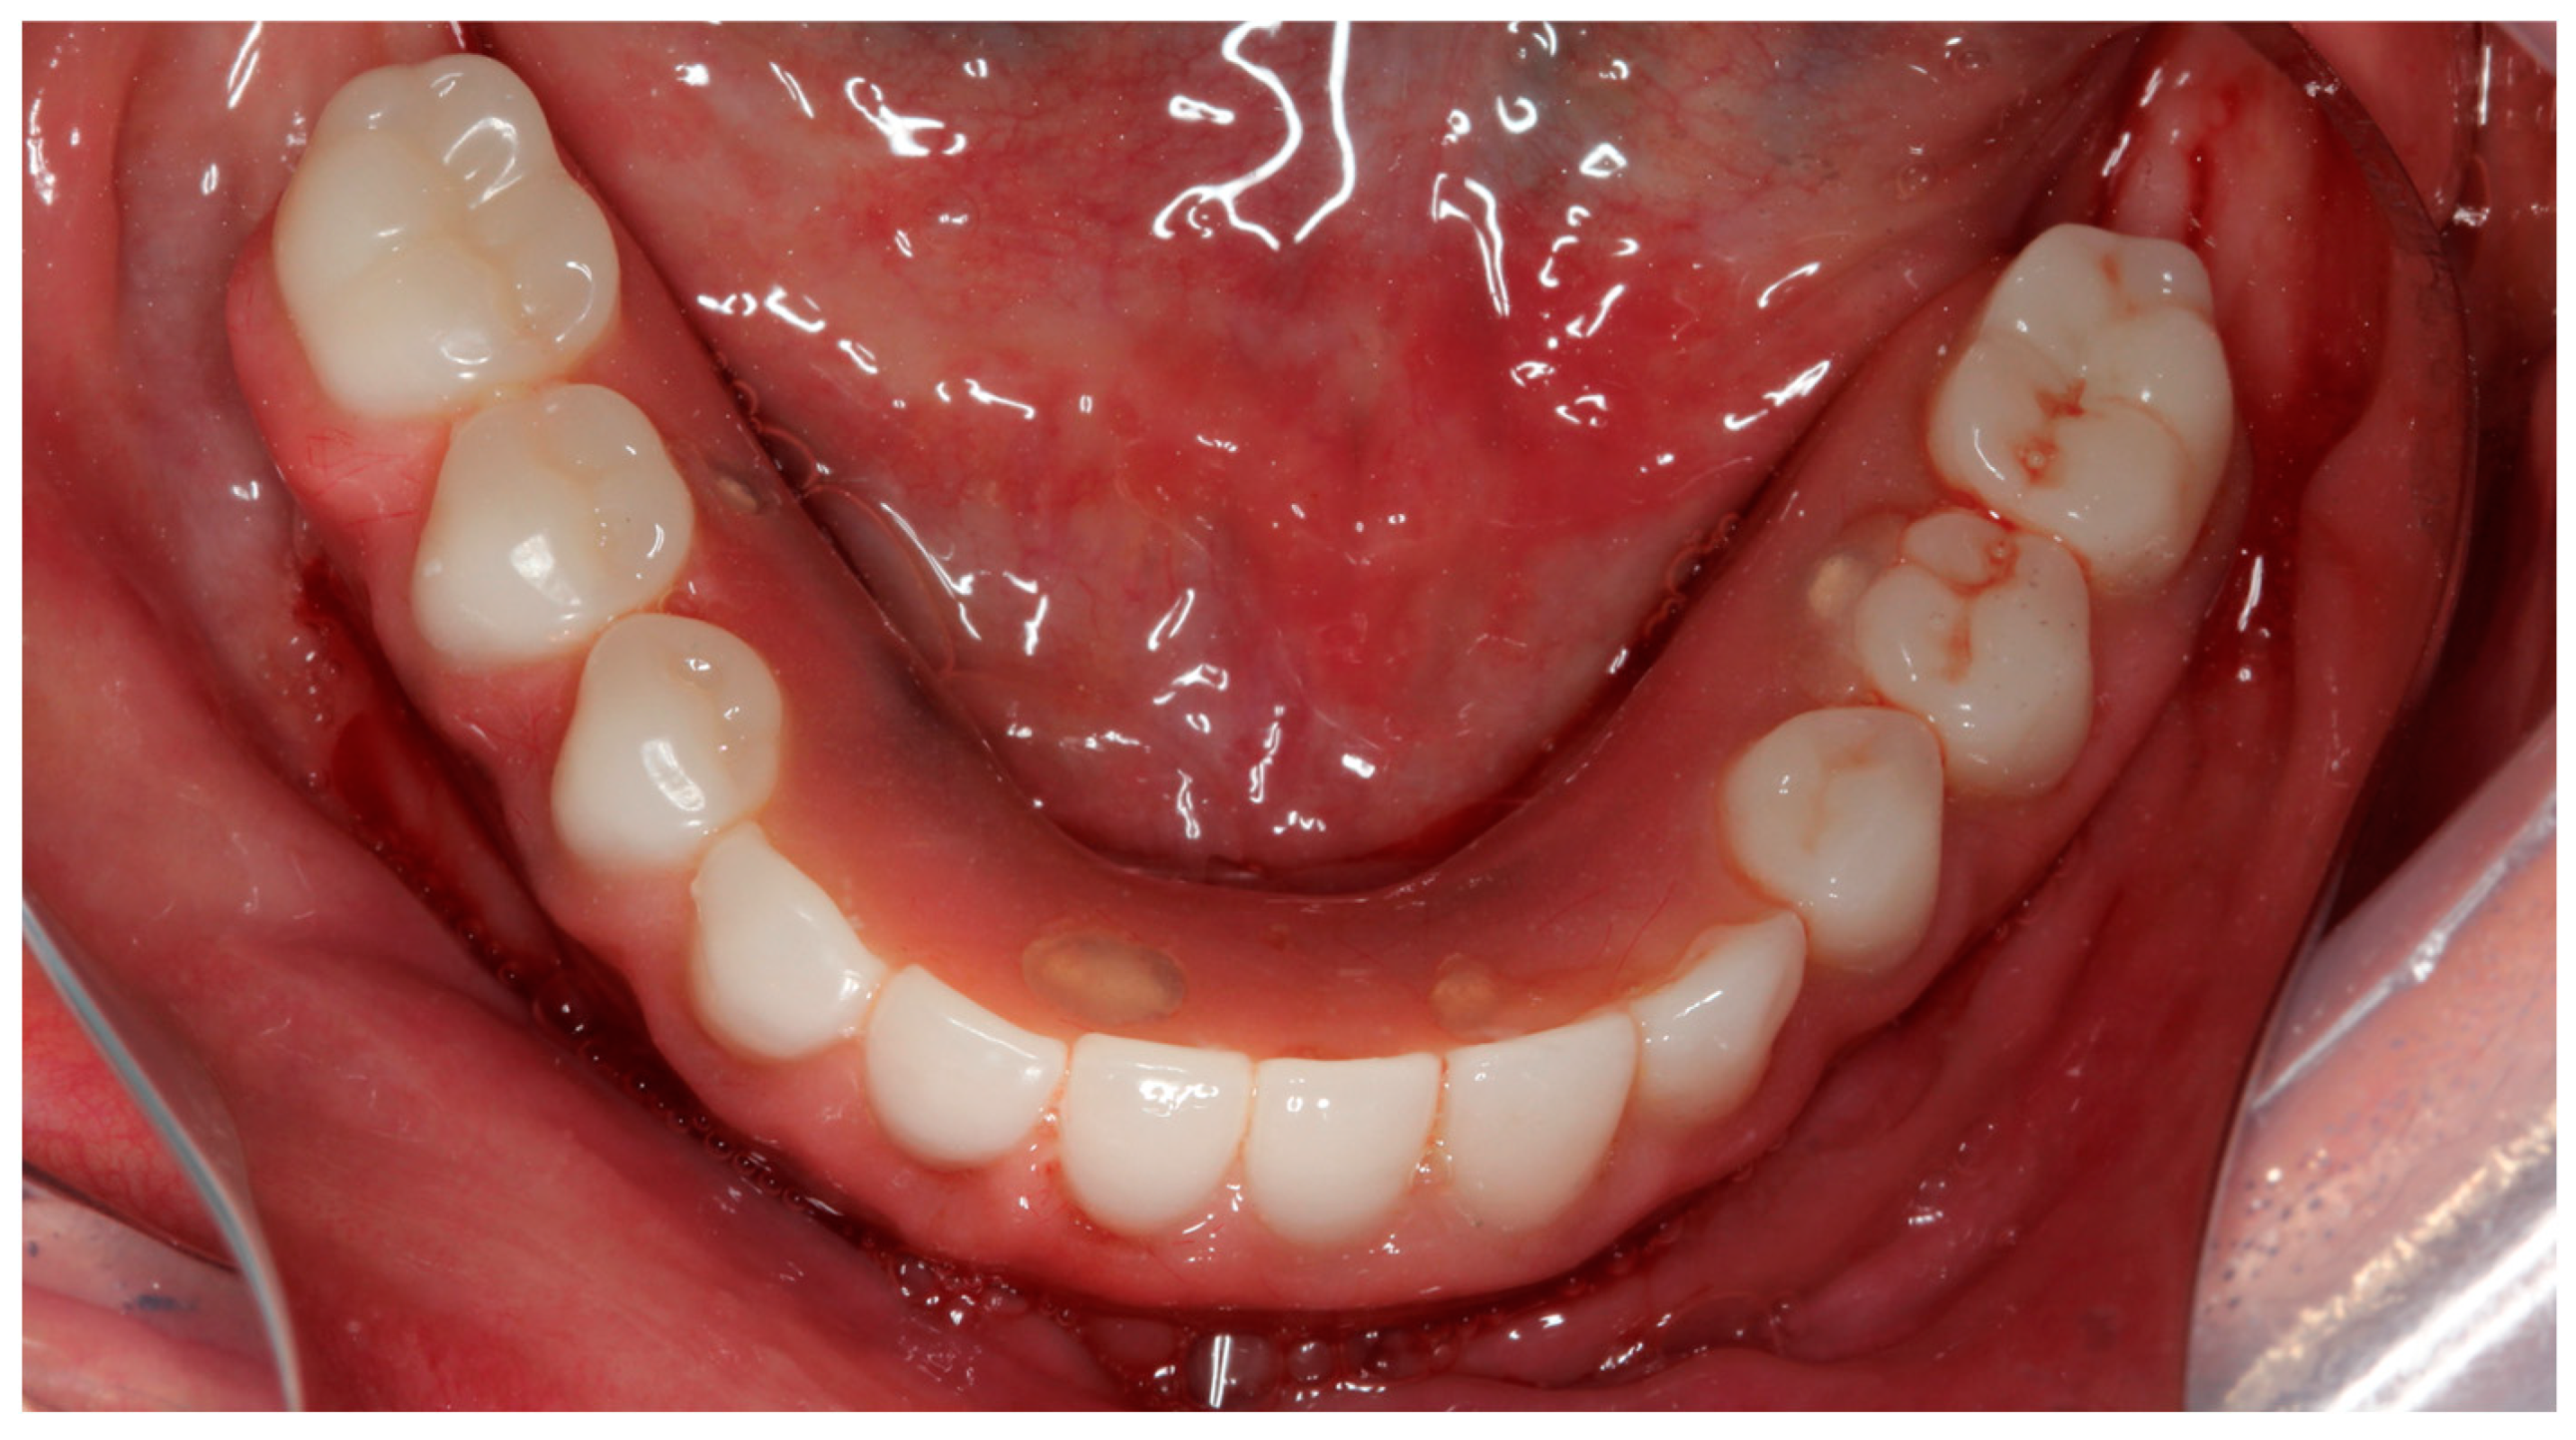

The installation and final occlusal adjustments of the full-arch rehabilitation occurred 48 h after surgery (Figure 11 and Figure 12).

Figure 11.

Occlusal view of the mandibular full-arch screw-retained rehabilitation 48 h after surgery.